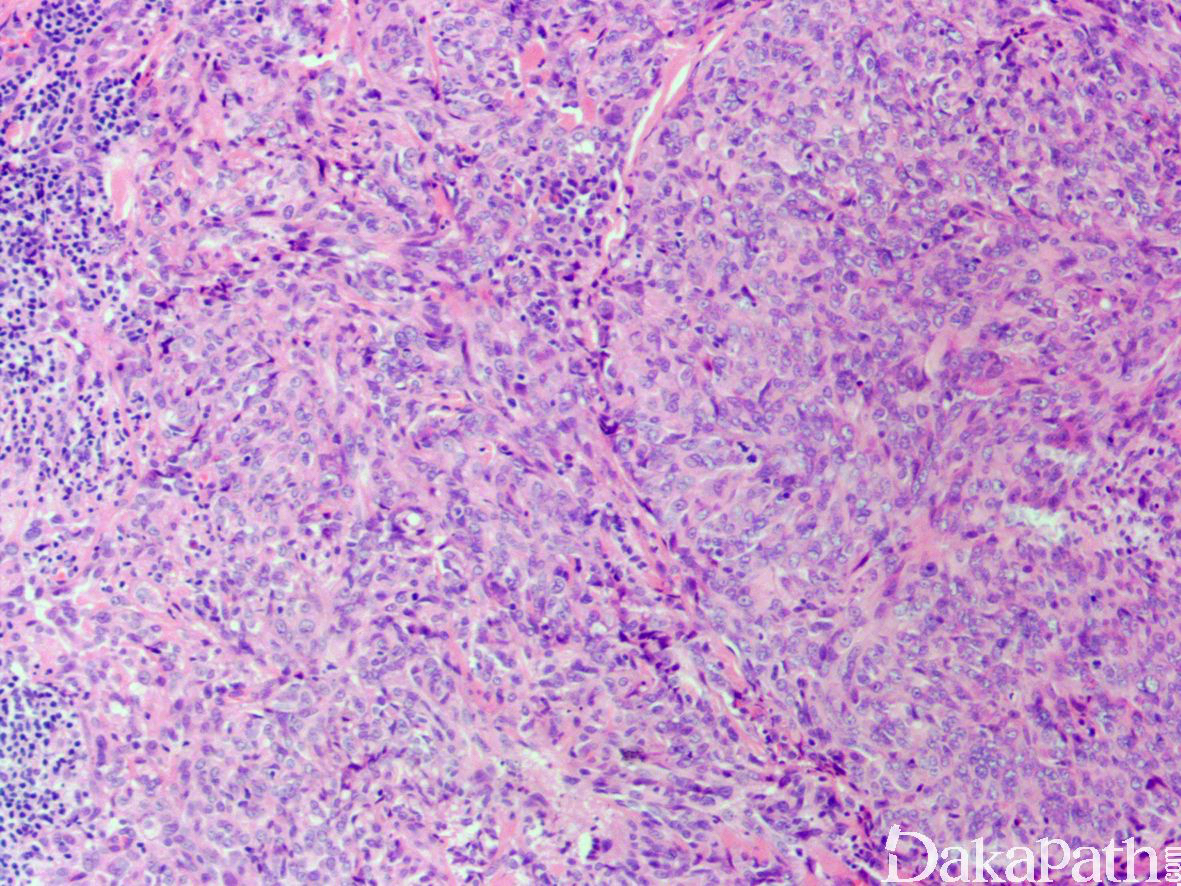

2,肿瘤位于浅表真皮或皮下,直径 0.8-8.5cm(平均 3cm),镜下肿瘤的整体上呈推挤状浸润性生长,边界周围和肿瘤内可见较多而致密的淋巴细胞浸润,有时可见生发中心形成;

肿瘤由分支状的血管腔隙被覆鞋钉样立方状内皮组成,内皮细胞核圆形深染,胞浆稀少,核可见折叠、核裂以及核内包涵体;

低倍镜下部分区域类似于网状血管内皮细胞瘤,表现为血管腔隙受压,被覆鞋钉样内皮以及管周纤维化增生,但管腔并不伸展,较短,类似于裂隙状微腺泡;异型性较大的细胞呈圆形

根据瘤细胞的组成和管腔结构的明显程度分为低级别和高级别,低级别肿瘤瘤细胞形态较温和,管腔结构明显,被覆多层瘤细胞;高级别肿瘤瘤细胞圆形,核仁明显,管腔结构不明显以实性生长为主。